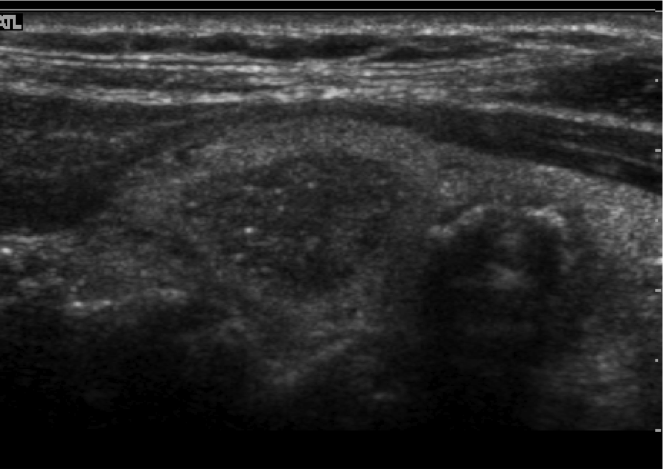

Complex nodule

Dx?